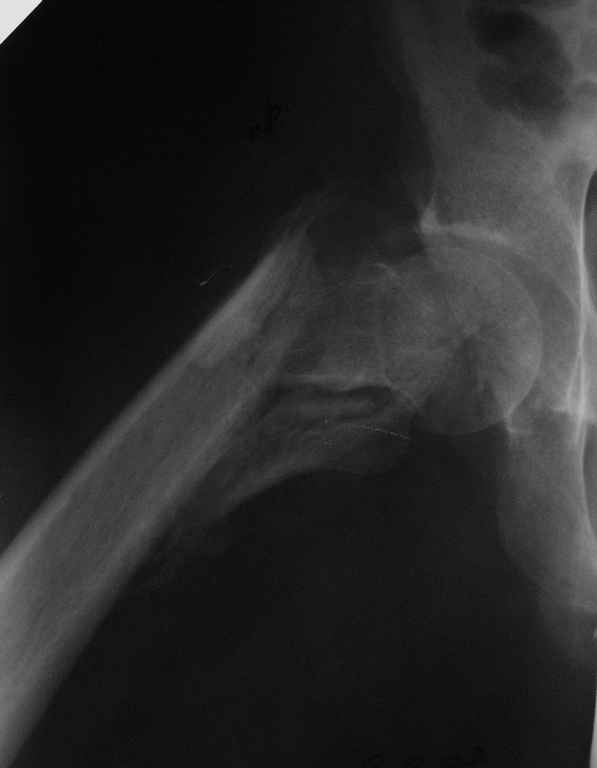

Пациент сорока лет с псевдартрозом правого бедра - исход оскольчатого чрезвертельного перелома с отрывом большого и малого вертелов. Поступил через 8 месяцев после травмы. По месту жительства лечили следующим образом: 2 месяца скелетное вытяжение, затем 2 месяца в кокситной повязке. После снятия гипса дали нагрузку. В настоящий момент имеется укорочение 6 см. Патологическая подвижность. По данным КТ - сращения нет, имеется аваскулярный некроз головки 2 стадии. В данном случае показано эндопротезирование тазобедренного сустава. Просим уважаемых коллег ответить на вопросы, которые возникли у нас по этому больному: 1. Имеет ли смысл выполнять первым этапом остеосинтез псевдартроза, учитывая, что нагрузка на сустав при наличии АНГБ противопоказана? 2. Возможно ли технически сразу выполнить эндопротезирование при наличии такого псевдартроза?

Вопрос в другом. 1) этот снимок не выглядит , как укорочение на 6 см. не понимаю

Форма головки сохранена, перелом, так скажем. не самый угрожающий в отношении ее "фатального" некроза.

Если имеются данные изотопного сканирования, кстати при начальных этапах это не всегда дает 100% результат, можно было бы выставить. А то на рентгенограмме не видно явлений, указывающих на АВН.